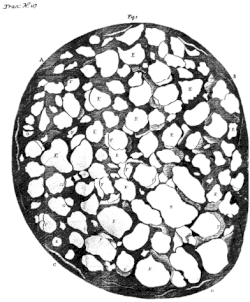

Гістологічна організація волокон

.jpg.webp)

2) Периневрій;

3) М'яка оболонка;

4) Павутинна оболонка та підпавутинний простір;

5) Тверда оболона.

Товщина нервових волокон (аксонів) нерва становить в середньому 10 мкм, середня кількість їх в одному нерві — півтора мільйона. Волокна преламінарної та ламінарної частин формують пучки та не покриваються мієліном; він вперше з'являється у ретроламінарній частині. Мієлін зорового нерва є центрального походження, тобто виробляється олігодендроцитами, що є ознакою того, що зоровий нерв є радше частиною ЦНС, ніж ПНС. У цих же ділянках волокна оточені астроцитами.[43][45][46] Вони відокремлюють нерв від тканини склери у ділянці решітчастої пластинки, утворюючи мембрану Джейкобі[47].

Така мікроанатомічна організація характерна для інших частин зорового нерва: формування пучків нервових волокон, які оточені астро-, мікро- та олігодендроглією[43][46].